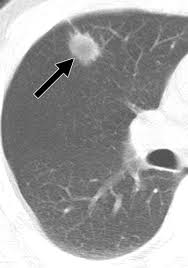

Or signs of lung cancer. Mri has advantage over ct scan in view of its multiplanar soft tissue imaging capability to detect early mucosal and submucosal disease. The most common signs of lung cancer are a cough that won't go away, chest pain, shortness of breath, weight loss, and fatigue. Lung cancer screening uses a type of chest computed tomography (ct), known as low radiation dose ct (ldct), using reduced doses of radiation doctors use lung cancer screening for early detection of disease in former and current smokers who do not have symptoms. The scan only takes a few minutes and is not painful. Like ct scans, mri scans show detailed images of soft tissues in the body. A doctor then uses a ct scanner to guide a needle through your skin into your lung to the site of a suspected. Early warning signs of lung cancer. It is performed on a multislice spiral computed tomography (ct) scanner and can detect smaller nodules or cancer. Some lung cancers can be found by screening, but most lung cancers are your doctor will also examine you to look for signs of lung cancer or other health problems. Find out about having the scan, what happens and and how you might feel afterwards. Store and/or access information on a device. Our doctors recommend lung cancer screening for people based on their age and the number of years they've smoked.

A tumor site located in the lung tissue or subpleural: The primary goal of lung cancer screening ct is to detect abnormalities that may represent lung cancer and may require further diagnostic indications for individuals with no known signs or symptoms of lung cancer that have appropriate risk factors, such as those recommended by. Changes in vesicular respirationpleural friction noise. Ct scan showing a cancerous tumor in the left lung. But mri scans use radio waves.

Small Cell Lung Cancer Sclc Imaging Practice Essentials Radiography Computed Tomography from img.medscapestatic.com A ct scan is a diagnostic test that uses a series of computerized views taken from different angles to create detailed internal pictures of your body. Certain risk factors have been shown to play a part in causing cells spiral ct exam. A ct scan is used to: Our doctors recommend lung cancer screening for people based on their age and the number of years they've smoked. A radiographer operates the scanner. Learn your real cancer risk from these scans. Most lung cancers don't cause symptoms until the disease has advanced, in part because the lungs have few nerve endings. Ct scan of the cervical spine.